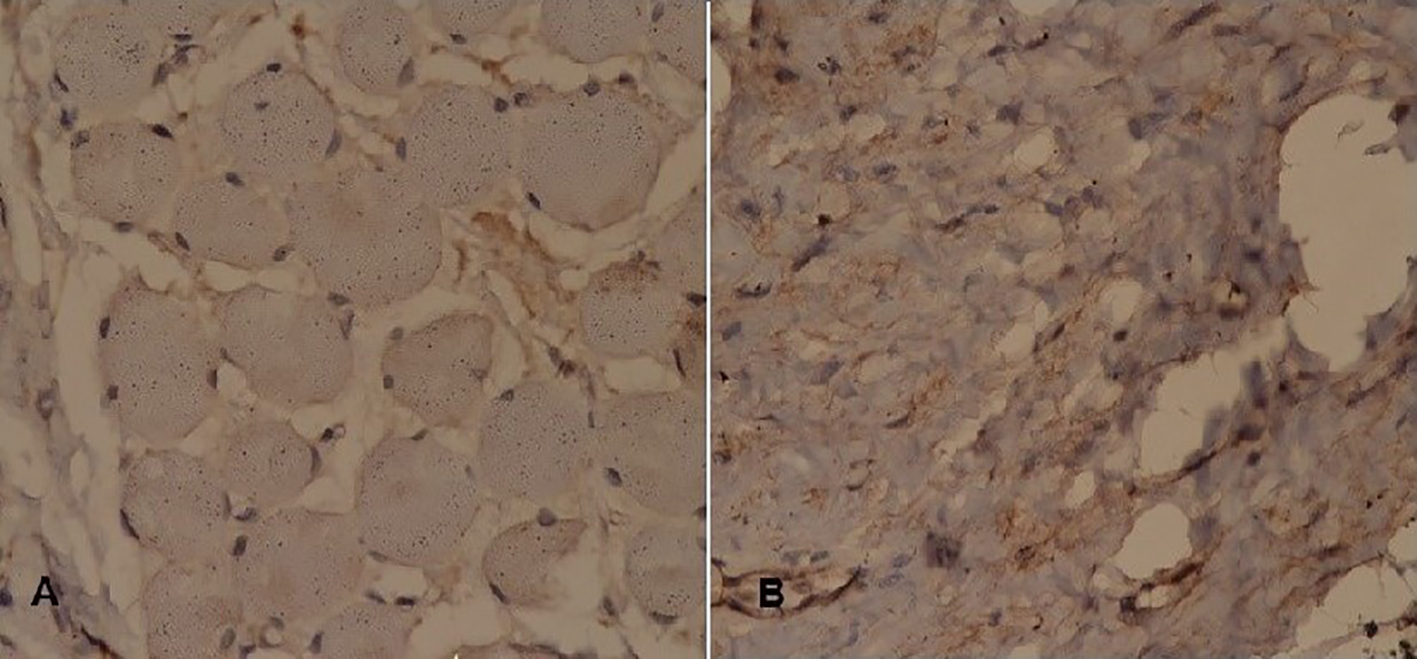

Postoperatively, patient recovered uneventfully. Histopathological assessment showed sheets of atypical spindle cells with large hyperchromatic nuclei, prominent nucleoli and abundant eosinophilic cytoplasm (Fig. 3). Positive immunohistochemical features (Table 1, Figs. 4, 5) included vimentin, anti-smooth muscle antibody (ASMA), myogenin and desmin in tumor cells, consistent with diagnosis of SC-RMS.

![]() Click for large image | Figure 4. Immunohistochemistry (1). Tumor cells stain positive for (A) desmin, (B) myogenin, (C) ASMA, and (D) vimentin. |

![]() Click for large image | Figure 5. Immunohistochemistry (2). Tumor cells stain negative for (A) CK AE1/CK AE3 and (B) S-100. |

Biopsy and immunohistochemistry constitute a great part in making a diagnosis. RMS is recognized on the basis of positivity for several immune markers including muscle specific actin, cytokeratin, myogenin, desmin, S-100 protein, vimentin and cytokeratin [15]. The histopathology in our case exhibited uniform positivity for ASMA, myogenin, desmin and vimentin that confirms cellular pattern of mesenchymal origin. S-100 was negative (thus differentiated from peripheral nerve sheath tumor) as well as cytokeratin AE1/AE3.